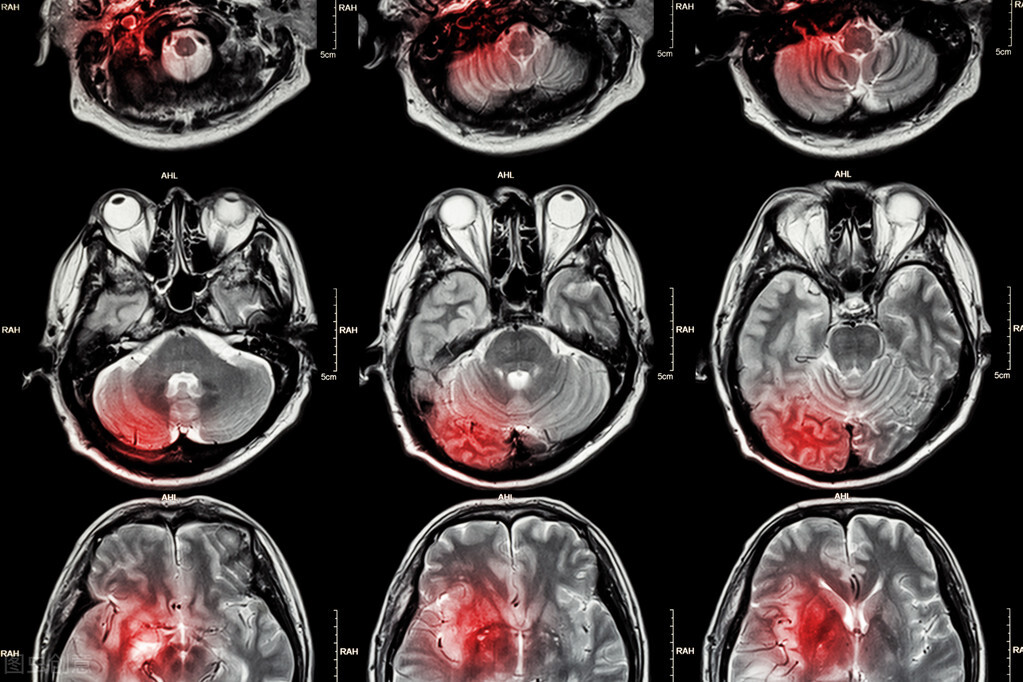

到了医院之后,医生发现刘女士因为高血压导致大面积脑梗,血氧饱和度不断降低,而且已经处于昏迷的状态,情况相当危险。医生赶紧将刘女士推进了抢救室进行抢救。

经过两个多小时的抢救,命是保住了,可是因为梗死的面积较大,刘女士在以后的康复过程中可能比较困难,也会留下明显的后遗症和偏瘫。

这还不是主要的,医生解释道,刘女士之所以会突发脑梗,其诱因是因为她晚饭后就立马去洗澡。当时她吃了咸鸭蛋之后,可能血压就已经升高,在浴室内狭窄封闭的空间温度急剧升高,会导致血管迅速扩张。而饭后全身血液主要供应到胃肠道,加上全身血管扩张,到达大脑的血液进一步减少,这样就引起大脑血管急剧缺血,引起缺血性脑卒中,也就是脑梗塞。

因此,刘女士的高血压是导致她脑梗的长期病因,而饭后立马洗澡是导致此次发病的急性诱因。